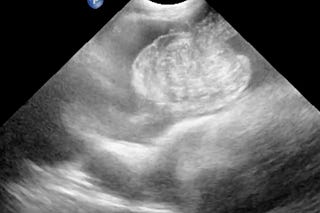

POCUS torácico en perros y gatos (IV)

Utilidad de esta técnica en estados de enfermedad.

POCUS torácico en perros y gatos (III)

POCUS torácico en perros y gatos (II)

Resumen de los conceptos y técnicas más relevantes de esta técnica diagnóstica.

POCUS torácico en perros y gatos (I)

Resumen sobre esta modalidad ecográfica en el diagnóstico de alteraciones pulmonares.